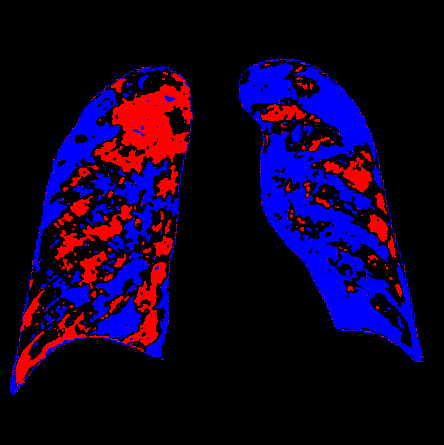

Side-by-side inspection of the generated healthy counterfactuals (as per fig. 2) suggests that, as required, only minimal perturbation is made to the original image with respect to healthy pixels -i.e. localized image sites without structural medical defects. (In the top row, the medical structural defect in the original image is due to a lung opacity, and characterized via a relatively complex interaction between the imaging modality and subject manifesting as ‘gaps’ in the corresponding portions of the lung scan). The healthy/non-healthy discrepancy maps in all of these cases are obtained via masked subtraction of the original image from the generated image (the ground truth segmentation masks correspond to the broad area of interest –i.e. the complete lung). The generated healthy tissue is thus a subset of the mask and is shown in the final column of fig. 2 for the respective cases.

In the context of a VANT-GAN[20]-based approach, this highlighted material constitutes the diagnostic counterfactual visual attribution, i.e. the selection of material relevant to the diagnosis of the unhealthy condition. Healthy counterfactual generation was performed for the complete datasets in the three unhealthy classes, i.e Lung opacity, Viral Pneumonia and COVID, examples of which are given in fig. 3 for the three classes (all of the generated healthy counterfactuals from this experiment can be found on https://huggingface.co/ammaradeel/diffusionVA). Visual inspection indicates that the generated counterfactuals are, in general, visually plausible with minimal perturbation made to the unhealthy image overall. Moreover, the healthy counterpart generation does not appear to unnecessarily affect aspects of the images unrelated to the medical condition, the model selectively making changes to the unhealthy regions in a structurally plausible manner, e.g. generating missing portions of the lung without generating extraneous lung material where it would be expected to normally exist (e.g. in the abdominal cavity).